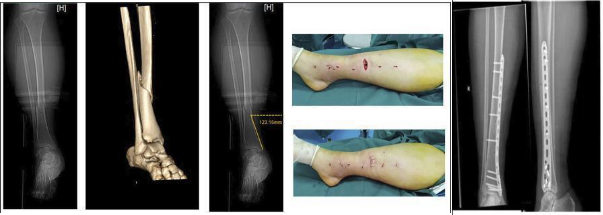

据庄全魁介绍,《四肢骨折微创治疗新技术(STMIPO)》是对微创接骨板技术(MIPO,即Minimally invasive plate oseoynthesis)的创新,MIPO最先用于治疗胫骨远端及股骨远端的骨折,距今已有30余年。因该技术不破坏骨膜血供,间接复位骨折,是最符合“BO”原则的骨折治疗方式。然而,其最大弊端在于骨折复位困难,常常导致很多临床医生放弃选择该技术,从而限制其在骨科临床中的应用传播。骨科二病区提出的STMIPO理论,即SecondTo Minimally invasive plate oseoynthesis,既兼顾MIPO技术微创理念,同时实现了直视下骨折复位的优势。这一研究成果不仅表明了我国在骨折治疗领域的重要贡献,同时也展示了阜阳市第二人民医院市级重点学科骨科的实力。